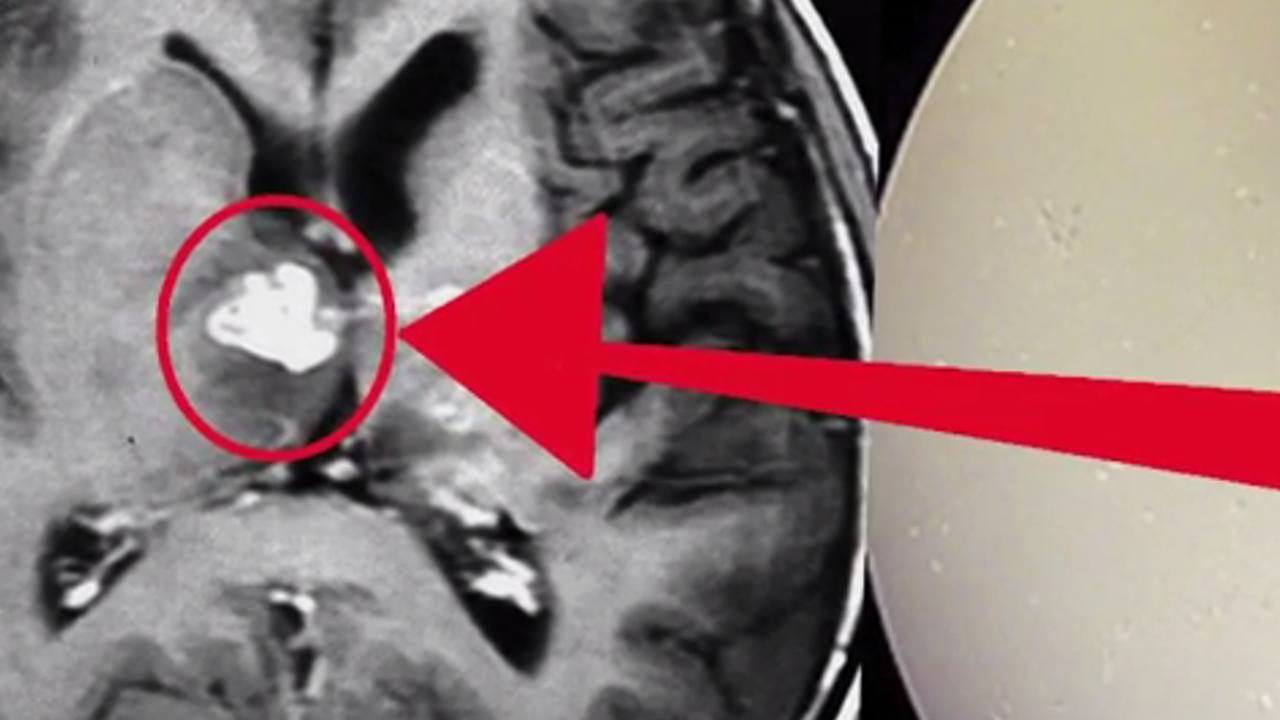

Centimetar dug crv izvučen je iz mozga Britanca koji se liječniku požalio na glavobolje, objavili su u petak znanstvenici i otkrili da je životinjica Spirometra erinaceieuropei četiri godine obitavala u mozgu 50-godišnjeg muškarca i selila se s jedne strane na drugu.

Crv izaziva upalu tkiva te gubitak pamćenja i glavobolje ako se nastani u mozgu.